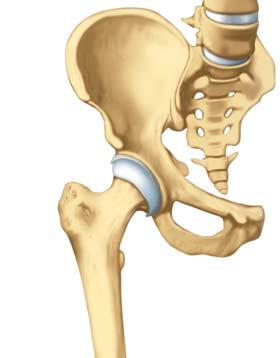

Beckenknochen

Hüftgelenkpfanne

Gelenklippe (Labrum)

Hüftkopf mit Gelenkknorpel

Oberschenkelhals

Grosser Trochanter

Kleiner Trochanter

Oberschenkelknochen

Anatomie der Hüfte

Die Hüftgelenke sind die zweitgrössten Gelenke unseres Körpers. Wir können sie weder ertasten, noch im Normalfall spüren. Was wir fälschlicherweise oft als Hüftknochen bezeichnen, ist der grosse Rollhügel oder Trochanter major. Dieser knöcherne Fortsatz befindet sich am oberen Ende des Oberschenkelknochens. Viele der Muskeln, die das Hüftgelenk bewegen, setzen dort an.

Was gehört zur Hüfte?

Die Hüftgelenke sitzen gut verborgen in der Leistengegend. Sie sind die Verbindung zwischen Oberschenkelknochen und Hüftpfanne, jener Einbuchtung im Beckenknochen, die im Idealfall genau auf den kugeligen Hüftkopf passt. Den Rand der Hüftpfanne umschliesst eine Art Dichtungsring, das Labrum. Für optimale Stabilität und Zentrierung des Gelenks sorgt eine elastische, sehr robuste Gelenkkapsel aus Bindegewebe.